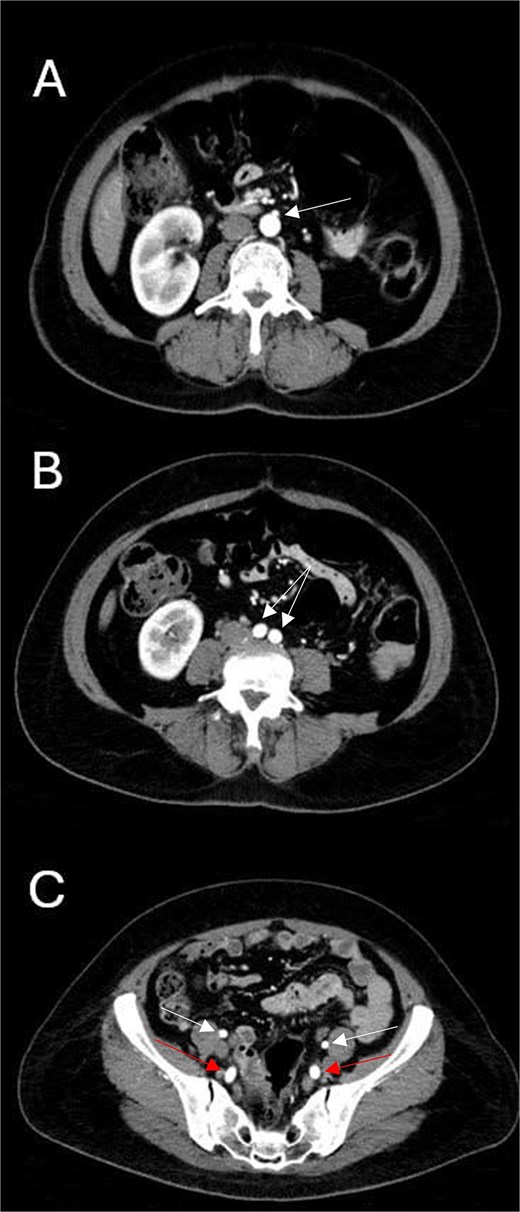

Subsequently, the patient underwent computed tomography angiography (CTA) of the lower extremities which revealed bilateral PSA (Fig. 1). The common femoral arteries trifurcated normally (Fig. 2), but the left superficial femoral artery (SFA) was significantly narrowed (Fig. 3). At the level of the knee, the right SFA joined the PSA to form the popliteal artery (Fig. 4). On the left side, the hypoplastic SFA converged with the PSA more proximally (Fig. 4); however, the artery was occluded, with no clear continuation into the popliteal artery (Fig. 4). Nevertheless, a markedly sub-occluded left popliteal artery was noted at the level of the fibular head, giving rise to a hypoplastic anterior tibial artery and tibio-peroneal trunk (Fig. 4). These findings align with Ahn-Min’s type I bilateral PSA (Fig. 5).

Axial CTA images show (A) the level of inferior mesenteric artery’s take-off from the abdominal aorta; (B) normal abdominal aortic bifurcation into common iliac arteries; and (C) bilateral prominent internal iliac arteries (lower arrows) and normal external iliac arteries (upper arrows).